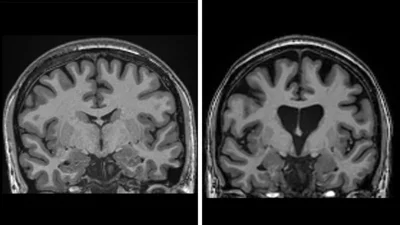

Янги усулнинг синовларини ташкил этган uniQurе компанияси 2022 йилда жарроҳлик амалиётини ўтказган ва кейин уч йил давомида кузатилган АҚШ ва Европадан келган кўнгилли беморларда Хантингтон касаллигининг ривожланиш даражаси 75 фоизга секинлашганини маълум қилди.

Хантингтон касаллигининг биринчи белгилари одатда 30 ёшдан кейин пайдо бўлади.Бемор бу касаллик билан 20 йилдан ортиқ яшамайди.

- Одатда бир йил давом этадиган заифлашув даври бор. Даволанишдан кейин 4 йил давом этади. Бу беморларга ўнлаб йиллар умр беради. Биз клиник ривожланишни 75 фоизга секинлаштиришни ҳеч қачон орзу қилмаганмиз, - деди тажриба иштирокчиси, клиник неврология профессори ва Лондон Университет коллежи Хантингтон касалликлари маркази директори Сора Табризий.